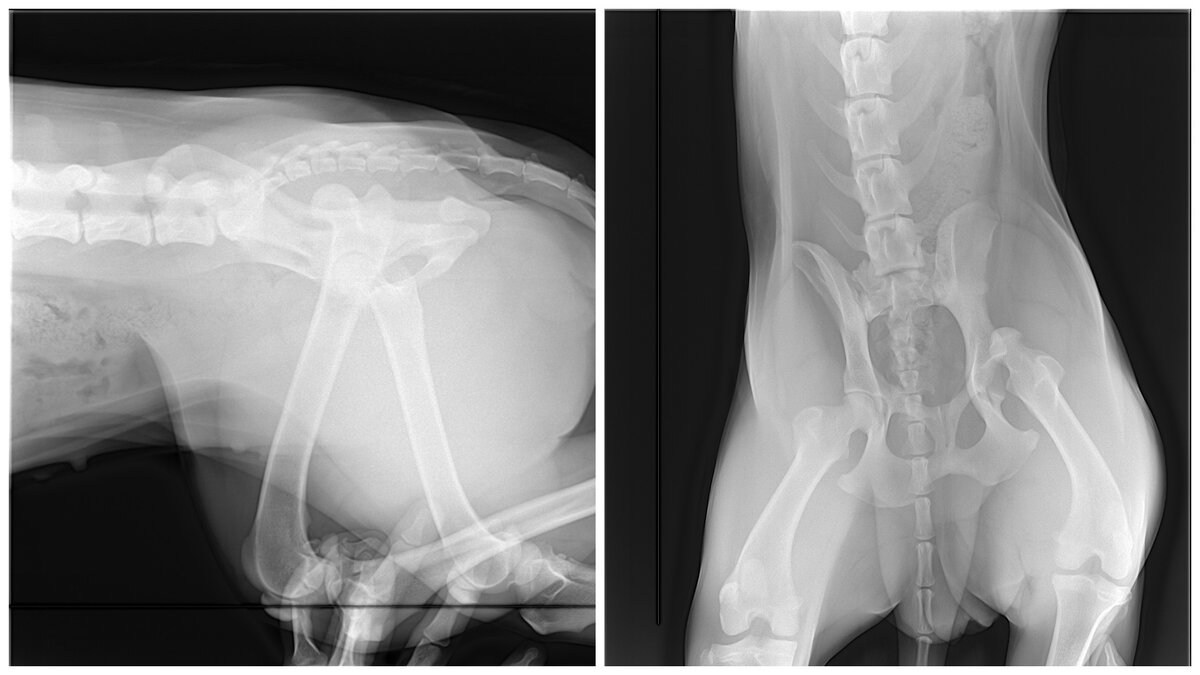

Снимки Лекси после случившегося. Видно, что кость не на своем месте.

В ветеринарной клинике нам диагностировали вывих. Сустав был выбит и поэтому была такая боль. Ветеринары нас сразу предупредили, что можно вправить и надеяться, что все будет хорошо, однако связка растянута и вероятность повторного выхода кости из сустава очень велика.

Тут уже видно, что все на своем месте и вроде бы ничего не предвещает беды.

А это видимо снимок с искусственной связкой, если я правильно понимаю...